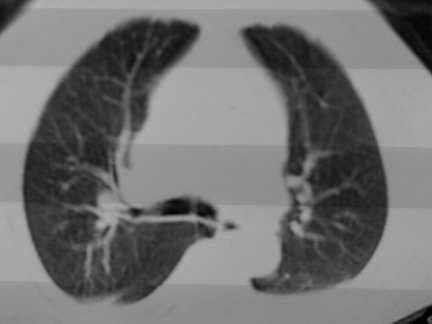

标题: CT13142:女 80 胸闷、气短、1w [打印本页]

标题: CT13142:女 80 胸闷、气短、1w

右肺炎性变

双侧胸腔积液

胸膜肥厚,

气管,支气管软骨钙化。

右肺感染;双侧胸腔少量积液,心影增大,可能与心功不全有关;胸内甲状腺肿。

胸内甲状腺肿;右肺感染;双侧胸腔少量积液。

胸内甲状腺肿;右肺中叶感染;双侧胸腔少量积液;心影增大,考虑有心功能不全。